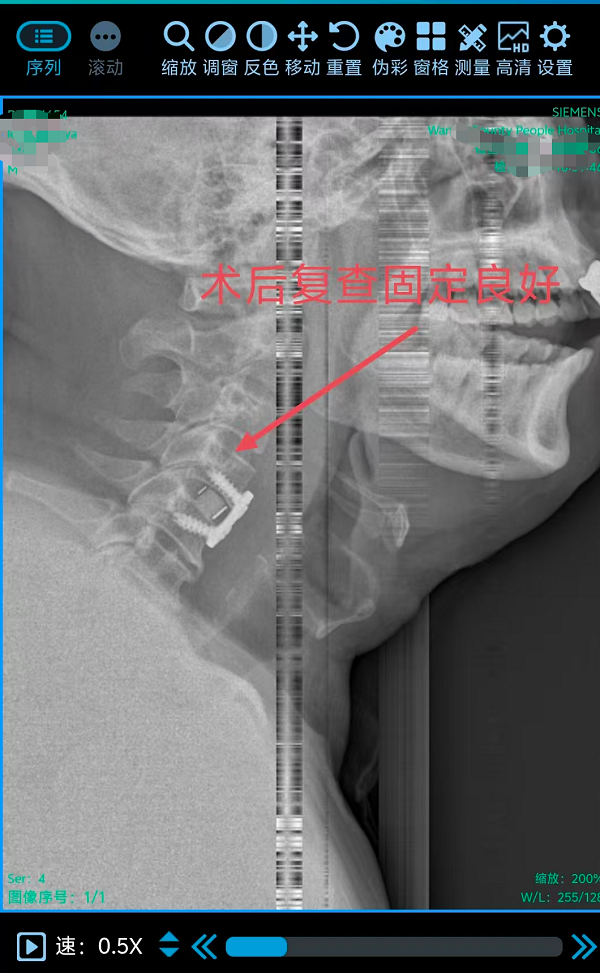

2. 为颈椎间盘巨大突出致肢体不全瘫患者行颈椎前路椎间盘切除融合内固定术(ACDF)(四级手术),该术式通过颈部前方的天然解剖间隙到达病变节段,在彻底解除脊髓和神经根压迫的同时,重建了颈椎的生理曲度和稳定性。手术团队凭借丰富的经验和精细的操作,在方寸之间精准完成了减压、植骨与内固定,有效避免了重要神经血管的损伤。

三台手术均顺利完成,患者术后恢复良好,标志着我院脊柱疾病微创化、精准化治疗迈上新台阶。